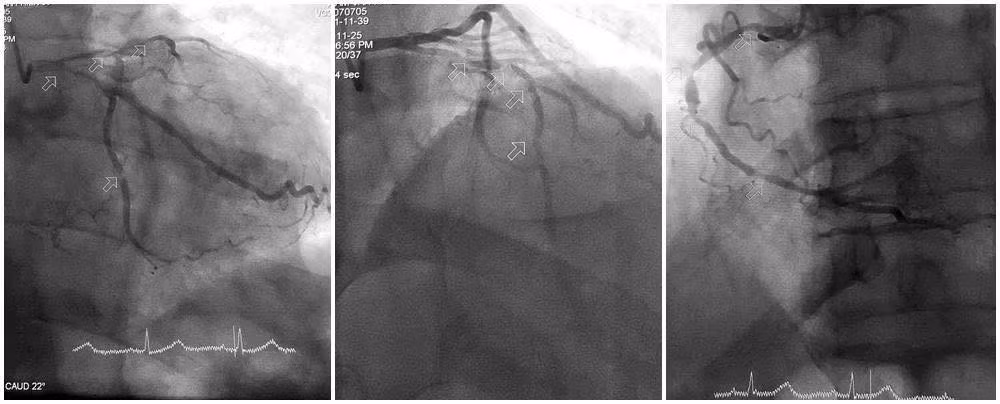

Đoạn mạch hẹp tắc tái thông sau can thiệp nong bóng và đặt stent - Ảnh BVCC

Kíp can thiệp tập trung xử trí tổn thương nặng, luồn dây dẫn qua đoạn mạch bị vôi hóa, sử dụng dụng cụ chuyên dụng để nong bóng, từng bước mở lại lòng mạch bị hẹp nặng.

Việc vượt qua các đoạn mạch vôi hóa cứng là thách thức lớn, song bằng kinh nghiệm và sự kiên trì, các bác sĩ đã đặt thành công stent vào đoạn động mạch liên thất trước bị nặng nề nhất, giúp tái thông dòng máu nuôi tim. Sau can thiệp, tình trạng huyết động của người bệnh dần cải thiện, nhịp tim ổn định, hết đau tức ngực.